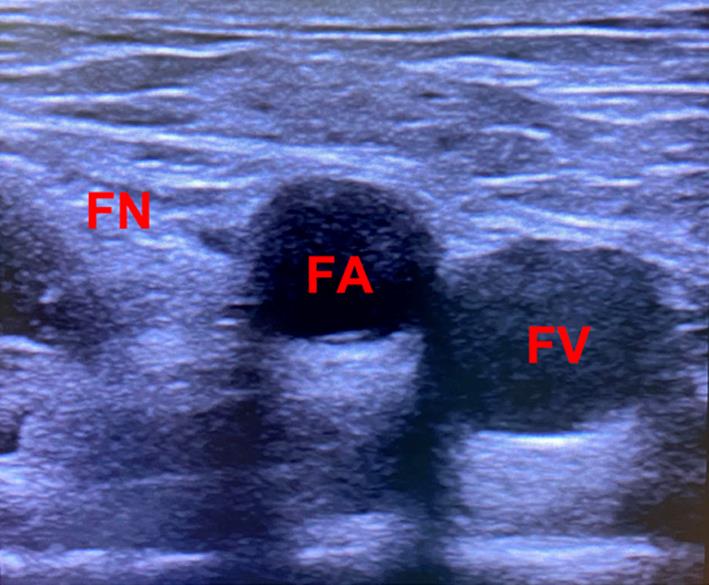

超声引导下股神经联合股动脉阻滞对下肢手术止血带反应的影响

Application of ultrasound⁃guided combined femoral nerve and femoral artery block on tourniquet response in lower extremity surgery

目的 观察超声引导下股神经联合股动脉阻滞减轻膝关节置换术患者止血带反应的安全性与有效性。 方法 选择择期行膝关节置换术治疗的患者100例,年龄18 ~ 75岁,体质量指数18 ~ 30 kg/m2 ,ASA分级为Ⅰ-Ⅲ级;采用随机数字表法随机分为超声引导股神经联合股动脉阻滞组(NA组)和单纯股神经阻滞组(N组),每组50例。两组均在麻醉诱导前行超声引导下目标区域阻滞,待确定阻滞效果后再行麻醉诱导。两组均在喉罩全麻下行手术,术后均予以自控静脉镇痛(PCIA)。术后若患者出现视觉模拟疼痛评分(VAS)> 5分则给予静脉注射氟比洛芬酯50 mg作为补救镇痛。记录患者麻醉前(T1)、止血带充气前1 min(T2)、止血带充气后15 min(T3)、30 min(T4)、45 min(T5)、60 min(T6)的SBP、DBP、HR,记录患者术中发生止血带高血压例数,记录患者术中尼卡地平、艾司洛尔的使用剂量,记录两组术后 2、6、12、24 h的动静态VAS评分,以及术后第1次补救镇痛的时间、补救镇痛的次数、首次下床活动时间和术后恶心、呕吐、谵妄、感染等不良反应发生的情况。 结果 与N组比较,NA组止血带充气后T5、T6时点的SBP、DBP、HR均显著降低,止血带高血压发生率和降压药使用剂量明显降低(P < 0.05),首次下床活动时间提前(P < 0.05);术后两组动静态VAS评分、第1次补救镇痛时间、补救镇痛次数以及术后恶心、呕吐、谵妄、感染等不良反应发生的情况差异无统计学意义(P > 0.05)。 结论 超声引导下股神经联合股动脉阻滞可安全有效地用于减轻膝关节置换术患者止血带反应中,且能够缩短术后首次下床时间,有利于患者的术后康复。

Objective To observe the safety and effectiveness of ultrasound?guided femoral nerve combined with femoral artery block to reduce tourniquet reaction in patients undergoing knee arthroplasty. Methods 100 patients(18 ~ 75 years old, body mass index 18 ~ 30 kg/m2)who were classified as grade Ⅰ?Ⅲ according to ASA standard and received unilateral total knee arthroplasty. The patients were randomly divided into two groups,the ultrasound?guided femoral nerve combined with femoral artery block with general anesthesia was utilized in group NA with 50 cases, and femoral nerve block alone with general anesthesia was used in group N with 50 cases. The target nerve block was guided by ultrasound before induction of anesthesia in both two groups,and anesthesia induction was performed after the block effect was etermined. Patients in two groups underwent surgery under general anesthesia of the laryngeal mask,and all patients under went self?controlled intravenous analgesia(PCIA). If a patient had a visual analogue score(VAS)score > 5 after surgery, flurbiprofenate 50 mg will be given intravenously as a remedy for analgesia. The patients' SBP,DBP and HR were recorded before anesthesia (T1), 1 min before tourniquet inflation (T2), 15 min after tourniquet inflation (T3), 30 min (T4), 45 min (T5), and 60 min (T6),the number of cases of tourniquet hypertension occurring in patients intraoperatively and the amount of nicardipine and esmolol were recorded, and the movement and static VAS scores at 2, 6, 12, and 24 h after surgery were recorded.the postoperative rescue analgesic requirements and the time of getting out of bed were recorded. The incidence of adverse reactions such as nausea,vomiting,deliriumand infection were also recorded. Results Compared with group N,SBP,DBP and HR were significantly lower in group NA at 45 and 60 min after tourniquet inflation, and the incidence of tourniquet hypertension and the amount of nicardipine and esmolol were also significantly lower (P < 0.05), and the time of getting out of bed was advanced (P < 0.05); the movement and static VAS scores,the time of the first remedial analgesia, and number of times of remedial analgesia, as well as the occurrence of nausea,vomiting,delirium and infection were not statistically significant. Conclusion Ultrasound?guided femoral nerve combined with femoral artery block can be safely and effectively used to reduce the reaction of tourniquet in patients with knee arthroplasty, and can shorten the time of getting out of bed after surgery, contributing to promoting postoperative rehabilitation.